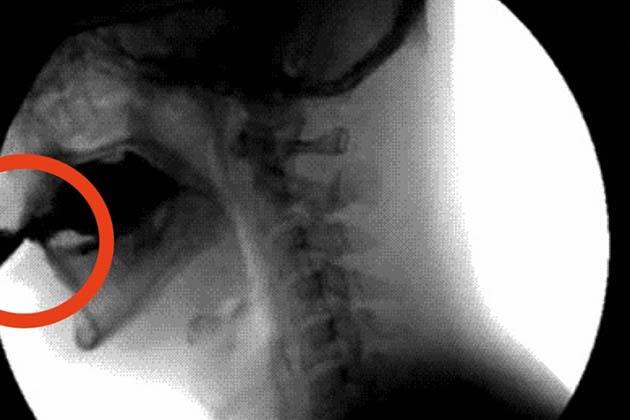

Quando a euforia finalmente passa, vem a hipoglicemia. Você se sente irritado e lento. Você perdeu toda a água contida na bebida de cola. E com ela se foram todos os nutrientes tão importantes para o bom funcionamento do seu corpo. Nutrientes que poderiam ter hidratado o seu corpo ou fortalecido os seus dentes e ossos. E para piorar, as chances de você desenvolver diabetes e ter de usar uma bomba de insulina como a da foto aumentam.